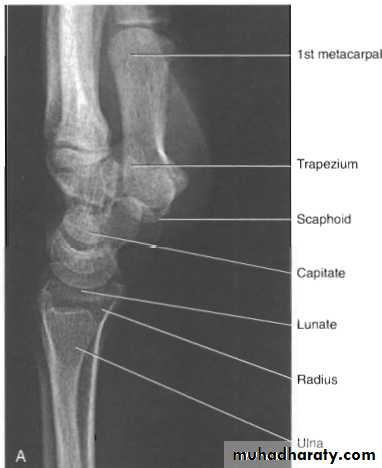

Radiological evaluation

Upper limbs

Lateral radiograph